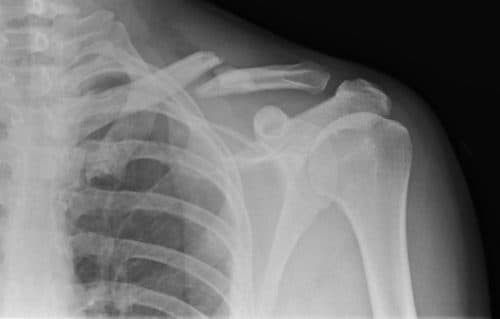

Gãy Xương Đòn Vai: Triệu chứng, nguyên nhân & Cách điều trị

Xương đòn có cấu trúc là mỏng, dẹt, nằm ở ngay dưới da, phía trước dưới vùng nền cổ, khi ta mặc áo hở cổ có thể nhìn thấy rõ xương đòn. Xương đòn vai rất dễ bị gãy cả trong trấn thương trực tiếp và trấn thương gián tiếp.

Triệu chứng gãy xương đòn

Các triệu chứng thường gặp khi bị gãy xương đòn vai dễ nhận biết là:

- Vùng xương đòn thường có vết bầm dọc, sưng, đau và bầm tím

- Vùng vai bị sụp hẳn xuống hoặc chùng xuống vì xương đòn bị gãy, không còn thực hiện được nhiệm vụ giữ và treo cánh tay với bả vai.

- Cơn đau tăng mạnh nếu như cố gắng cử động dang cánh tay.

- Vùng vai bị biến dạng, xương đâm ra khỏi da. Cần phải nhanh chóng đưa người bệnh đến cơ sở y tế chuyên khoa để sớm khắc phục tình trạng bệnh.